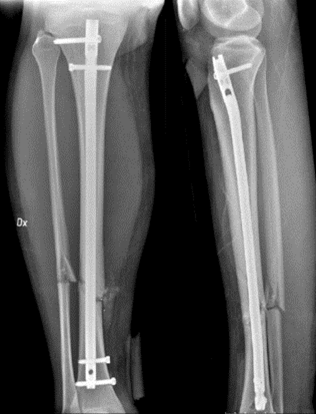

Beskriv frakturen

• HÖGER UNDERBEN

o Mittdiafysär komminut (splittrad) tvärfraktur fibula, dislocerad (halv benbredd)

o Mittdiafysär spiralfraktur tibia, dislocerad (halv benbredd)

o 12-13 cm proximalt om fotleden.

Sluten reposition (perfekt placering av ben) och märgborrning samt märgspikning med interlocking nail.

Röntgen

Henrik opereras akut med sluten reposition (perfekt placering av ben) och märgborrning samt märgspikning med interlocking nail.